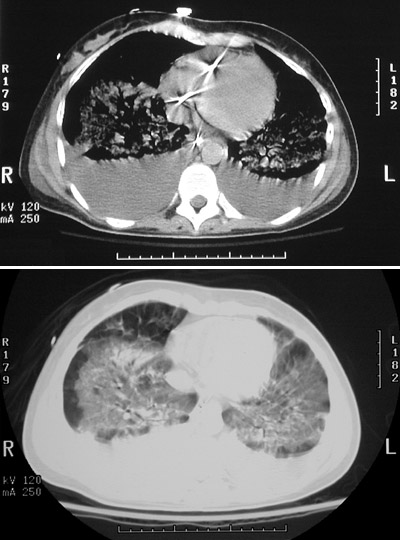

| Here is a chest CT scan of a patient with multiple organ failure syndrome in the intensive care unit. One component of this syndrome is pulmonary diffuse alveolar damage with opacifications in all lung fields, seen best in the soft tissue window setting in the lower panel. The upper panel in lung window setting reveals the opacifications as well as prominent posterior effusions. (A Swan Ganz catheter traversing the right heart is scattering the x-rays to produce the star-shaped areas of brightness in the upper panel.) |